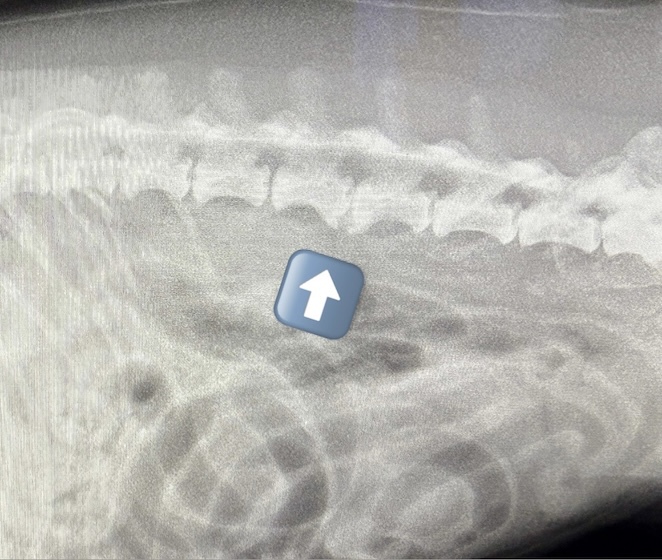

変形性脊椎症(2025/12/08)

変形性脊椎症は、身体を支えている背骨(脊椎)が年齢とともに少しずつ変形してしまう病気です。多くは無症状なためレントゲン検査で偶然見つかることも珍しくありません。しかし、変形した脊椎が神経を圧迫することで痛みや歩行異常が現れることがあります。椎間板の変性や加齢による椎体間の不安定性が原因と考えられています。症状が見られる場合は、鎮痛剤で痛みを和らげたり、温熱療法などの理学療法で筋肉の緊張をほぐしながら経過を見ていきます。最近活動量が減ってきた、歩きにくそうにしている、などの変化は病気のサインかもしれません。なにか気になる症状があればお気軽にご相談下さい。

犬の変形性脊椎症(2024/12/07)

変形性脊椎症とは身体の構造を支えている脊椎に変形が起こってしまう病気です。多くは無症状で健康診断などで偶発的に発見される事があります。しかし変形した脊椎が神経を圧迫する事でまれに痛みや運動障害を引き起こす事があります。治療は症状がある場合は鎮痛剤の投与や、温熱治療などの理学療法を行って痛みを緩和していきます。また肥満の場合には脊椎に過度な負荷をかけてしまうため、適切な体重管理が重要となります。お家のわんちゃんが高齢になって活動性が落ちてきた、歩きにくそうにしているなど気になる症状がありましたら、お気軽にご相談ください。

変形性脊椎症(2024/02/06)

脊椎に骨増殖と呼ばれる変形が起きる疾患で、加齢に伴い発症率は上昇します。多くは無症状ですが、一部は慢性的な痛みを生じて日常生活に支障を来たすこともあります。持続的な脊椎への負担や椎間板の変性などが原因と考えられており、痛みがある際には消炎鎮痛剤の内服や運動制限、温熱療法などの治療が推奨されます。動きが鈍い、歩きづらそうなどの症状がある場合にはお早めにご相談下さい。